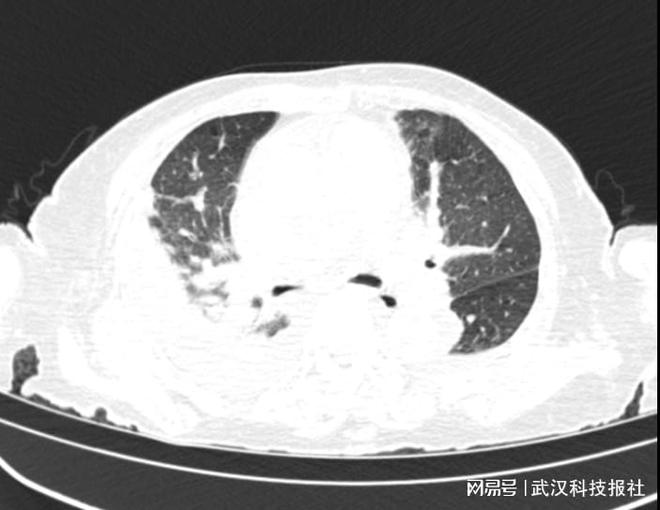

心率150 次/分的房颤、双肺湿啰音、下肢重度水肿,急性心衰已让99岁的熊奶奶(化名)命悬一线;意识嗜睡、言语不清、肌力下降的神经症状,更让病情雪上加霜。面对这一“心衰+神经损伤”的双重危情,武汉市汉口医院神经外科团队突破高龄救治难题,助老人转危为安。99岁高龄双重危情 心衰叠加神经异常命悬一线岁的熊奶奶因“突发心慌胸闷、言语模糊1天”被紧急送往武汉市汉口医院,入院时,熊奶奶病情凶险:心率飙升至150次/分(房颤),血压150/80mmHg,双肺出现湿啰音,双下肢重度水肿,被确诊为急性心力衰竭。更令人揪心的是,还伴随意识嗜睡、精神萎靡、言语不清、四肢肌力下降(4级)等神经功能异常症状,陷入“心衰+神经损伤”的双重危局。武汉市汉口医院神经外科团队接诊后指出,熊奶奶作为超高龄患者,大脑对缺血缺氧耐受性极低,心衰导致的全脑低灌注是神经症状的重要诱因,且高龄与快速房颤使其面临极高的脑卒中、心源性脑栓塞风险。若仅聚焦心衰治疗,忽视神经功能障碍,可能引发不可逆脑损伤,救治需兼顾心肺稳定与神经保护,难度极大。

面对复杂病情,武汉市汉口医院神经外科团队果断扛起救治重任,制定以“神经保护为核心”的综合救治方案。在诊断环节,团队迅速为熊奶奶完成神经系统全面查体,优先安排头部CT/CTA等影像学检查,精准鉴别其神经症状。